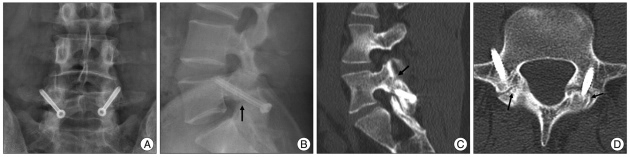

Pars Vidalama